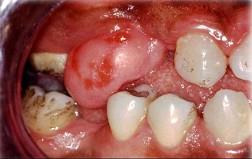

组图为口内纤维瘤的外观,关于此病的描述不正确的是 ( )

组图为口内纤维瘤的外观,关于此病的描述不正确的是 ( )![]()

A生长一般较缓慢

B手术后不易复发

C主要由纤维组织构成

D有可能恶变

E肿瘤边界清楚